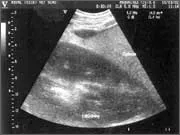

Thoracic and abdominal ultrasonography

This is a key diagnostic technique in the hospital and the technology has advanced to such a degree that we are able to image blood flowing within the heart and collagen fibre misalignment in tendons.